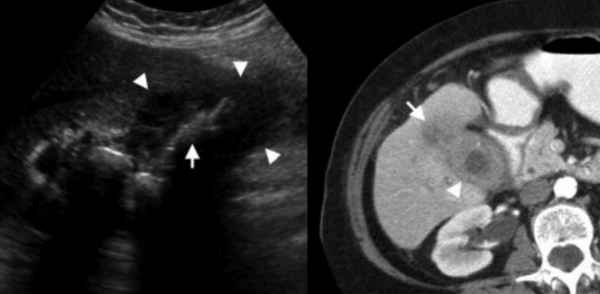

(Слева) На поперечной трансабдоминальной сонограмме в ямке желчного пузыря визуализируется эхогенная структура изогнутой формы с акустической тенью — изменения, характерные для «фарфорового» желчного пузыря.

(Справа) На сонограмме визуализируется стенка желчного пузыря с диффузно повышенной эхогенностью и объемное образование в области его дна. Задняя стенка желчного пузыря различима, в отличие от эмфизематозного холецистита или множественных камней, заполняющих желчный пузырь. При патоморфологическом исследовании были обнаружены интрамуральные кальцинаты, признаки хронического холецистита и аденокарциномы желчного пузыря.